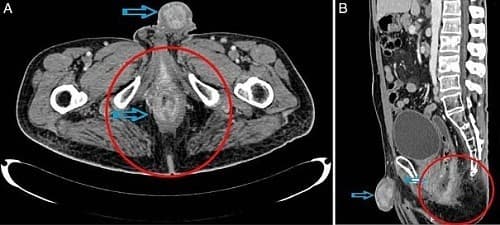

Triệu chứng của ung thư dương vật thường thay đổi theo từng giai đoạn bệnh. Hình ảnh ung thư dương vậy này cho thấy bệnh đã ở giai đoạn nặng, khối u phát triển to lên, và có thể di căn sang các vị trí khác trong cơ thể.

Để quan sát kỹ hơn hình ảnh ung thư dương vật thì ngoài thăm khám bằng tay cần phải tiến hành siêu âm. Nhiều trường hợp cần tiến hành chụp X-quang, chụp MRI/CT để xác định mức độ di căn của bệnh.